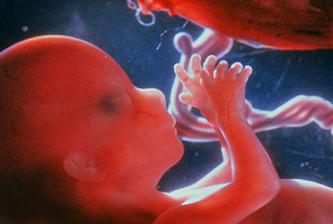

zázrak lidské života na videu